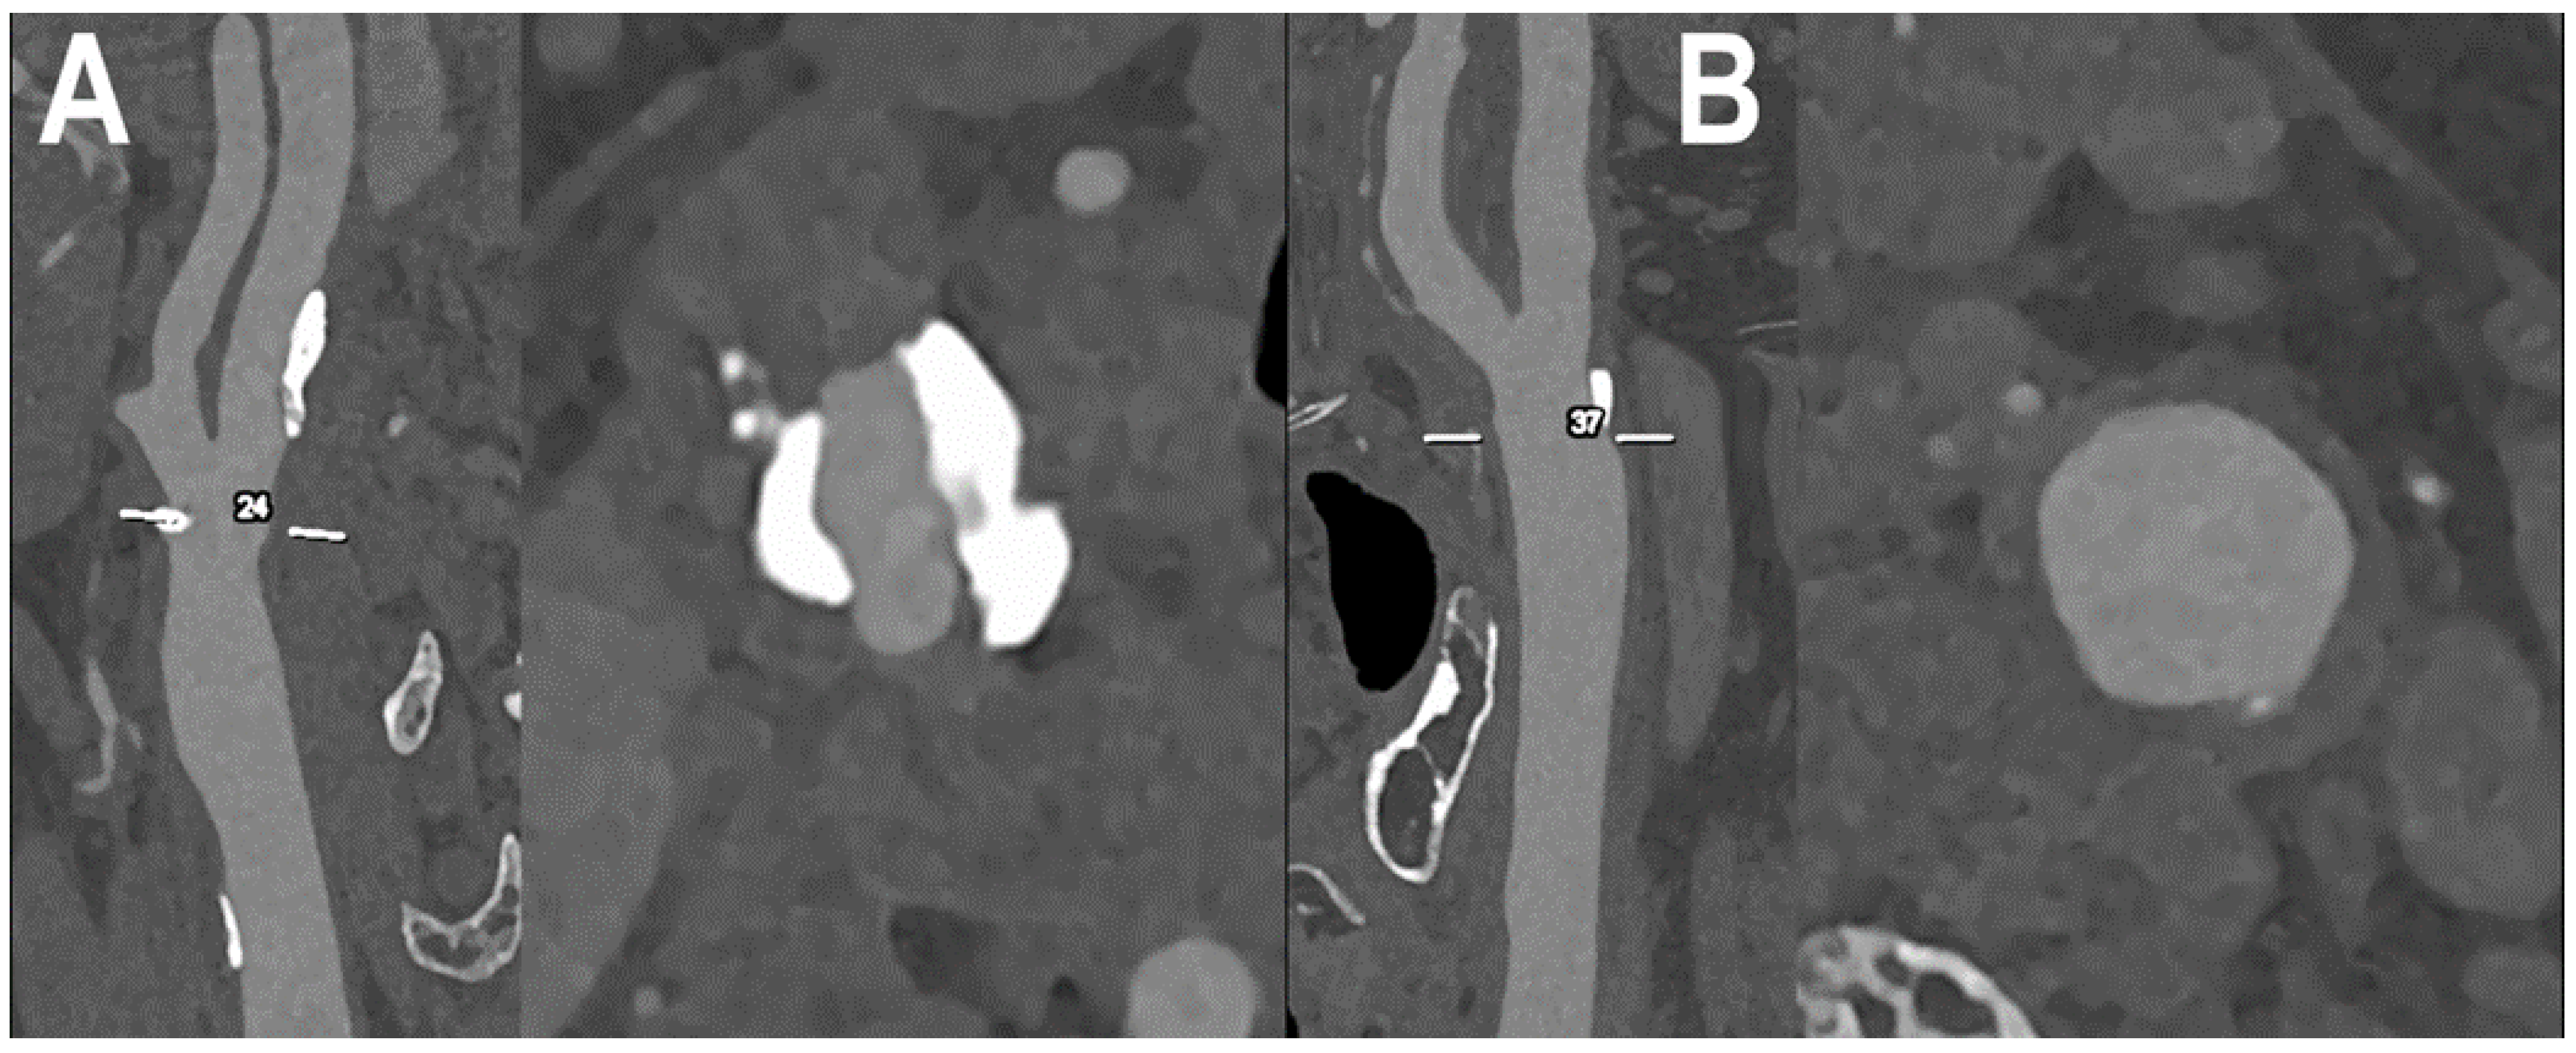

| Michael et al. [28] | 2022 | In vivo (human) | 37 | Iodine-only images | The most favorable contrast-to-noise-ratio and signal-to-noise-ratio were detected in the PER and low keV MER. In the qualitative image analysis, the PER was superior to the MER in all rated criteria. For MER, 60–65 keV was rated as best image quality. |